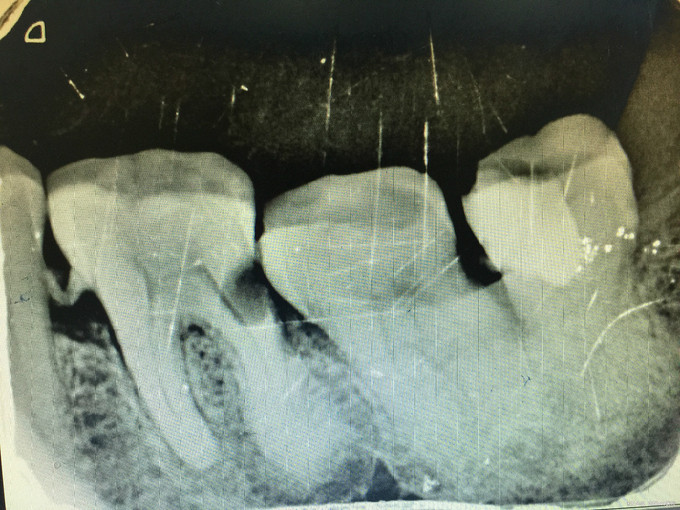

临床检查:36远中邻面龋坏,探疼(+),冷(++),叩(-)可探及穿髓点,无窦道,松动度(-),牙周正常. 辅助检查:X线示36远中龋坏累积髓腔。

诊断:36牙髓炎 治疗:经患者知情同意后,36局麻去腐降牙合,开髓拔髓寻找根管口,建立直线通路,扩通根管,确定工作长度。vdw/EDTA凝胶镍钛器械,低浓度次氯酸钠冲洗根管,预备至25/06,氢氧化钙诊间封药,一周后复诊,试主尖X线示恰充,试干根管,导AH-PLUS糊剂,VDW热压胶垂直加压根充,术后见根管恰充,暂封嵌体修复。